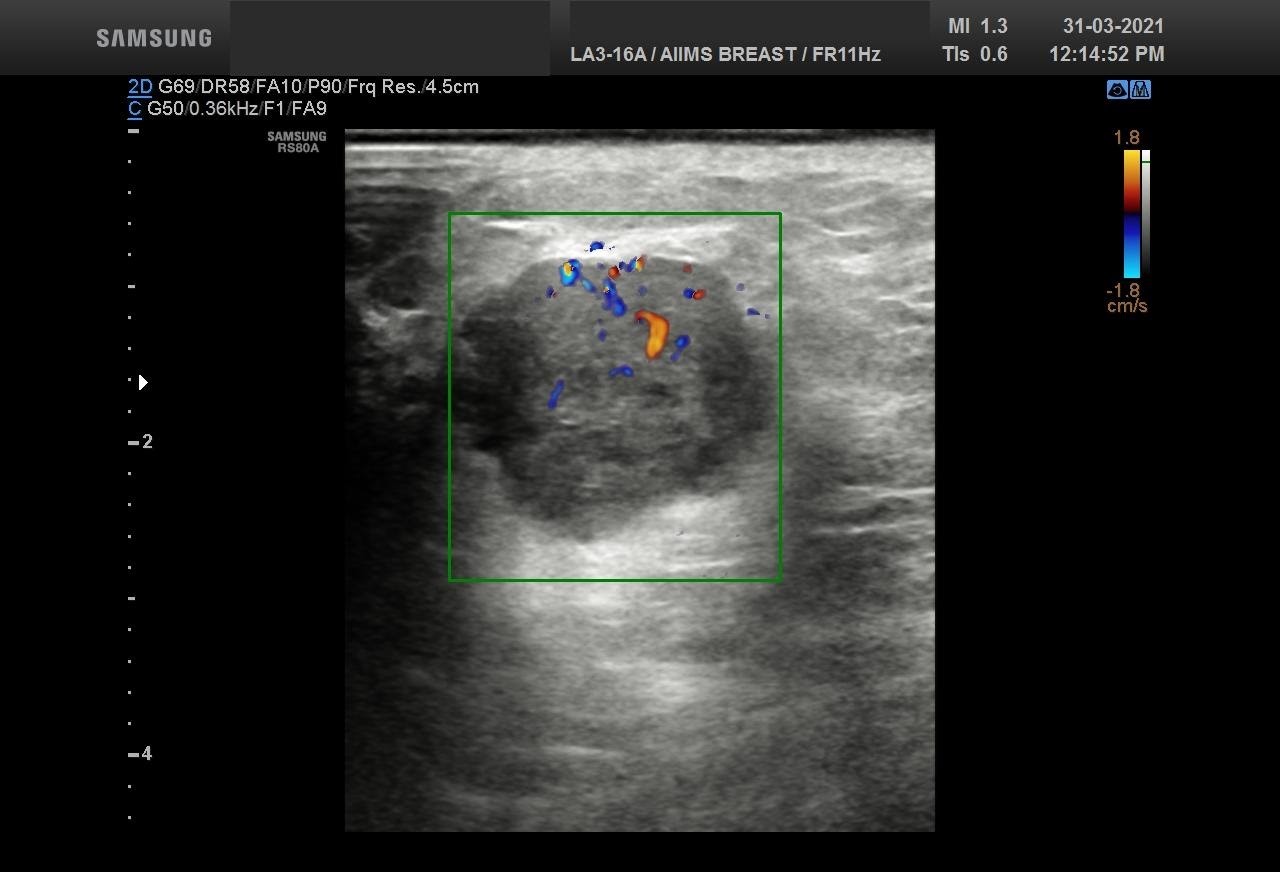

Bilateral Digital mammography , Craniocaudal (CC) and Mediolateral oblique (MLO) view with tomosynthesis images revealed a round shaped, equal density mass with indistinct margin in lower outer quadrant. No suspicious microcalcifications was seen. No significant axillary lymph nodes were present. A high resolution ultrasound of the right breast showed a round shaped, heterogeneously hypoechoic mass with irregular margin, small cystic spaces within and posterior acoustic enhancement, measuring about 1.6x1.9x1.5cm at 7 O’clock position. Mild internal vascularity was noted on colour doppler images. Right axilla showed suspicious lymph nodes with loss of fatty hilum and thickened cortex.